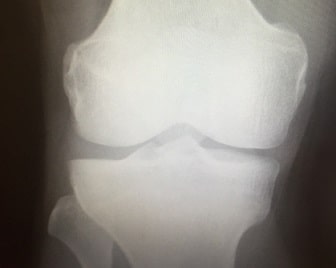

オスグッド・シュラッター(Osgood-schlatter)はひざのお皿(膝蓋骨)の下のすねの骨(脛骨・けいこつ)の脛骨結節という少しでっぱった部分が炎症をおこして痛む病気です。

子どもの脛骨結節は、成長過程であり、まだ柔らかく、激しい運動のストレスに耐える強度が低くいので、ジャンプやランニングを繰り返すと、筋肉に引っ張られる結果、筋肉の付け根の骨に細かいひびができて炎症を起こしてしまいがちです。

一般的には成長痛といわれて、放置されることが多く、遊離骨片といって骨がかけるような終末期の状態で初めて真剣に向き合うことが多い病気です。